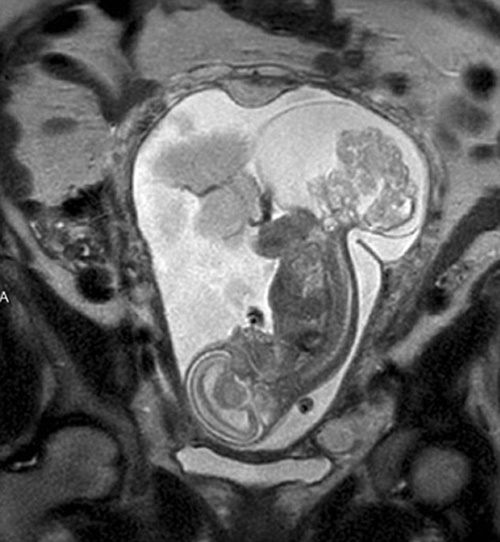

Hình ảnh siêu âm của bé Lynlee (Ảnh: dailymail). |

Niềm hy vọng sống sót duy nhất của em khi đó là một cuộc phẫu thuật kéo dài 20 phút vào tuần thai thứ 23 để mở tử cung người mẹ. Thời điểm đó, em chỉ mới nặng gần 540gr, các bác sĩ đã tiến hành mổ cắt bỏ khối u rồi đưa em lại vào trong tử cung của mẹ. Khối u được đo có kích thước bằng với thai nhi. Chị Margaret sau đó đã được yêu cầu nằm yên trên giường suốt cho đến gần tuần thai 36. Và rồi bé gái Lynlee Boemer đã chính thức chào thế giới bằng phương pháp sinh mổ với cân nặng hơn 2,4kg. Sau đó em đã được đưa đi kiểm tra sức khỏe và đưa vào phòng dưỡng nhi.